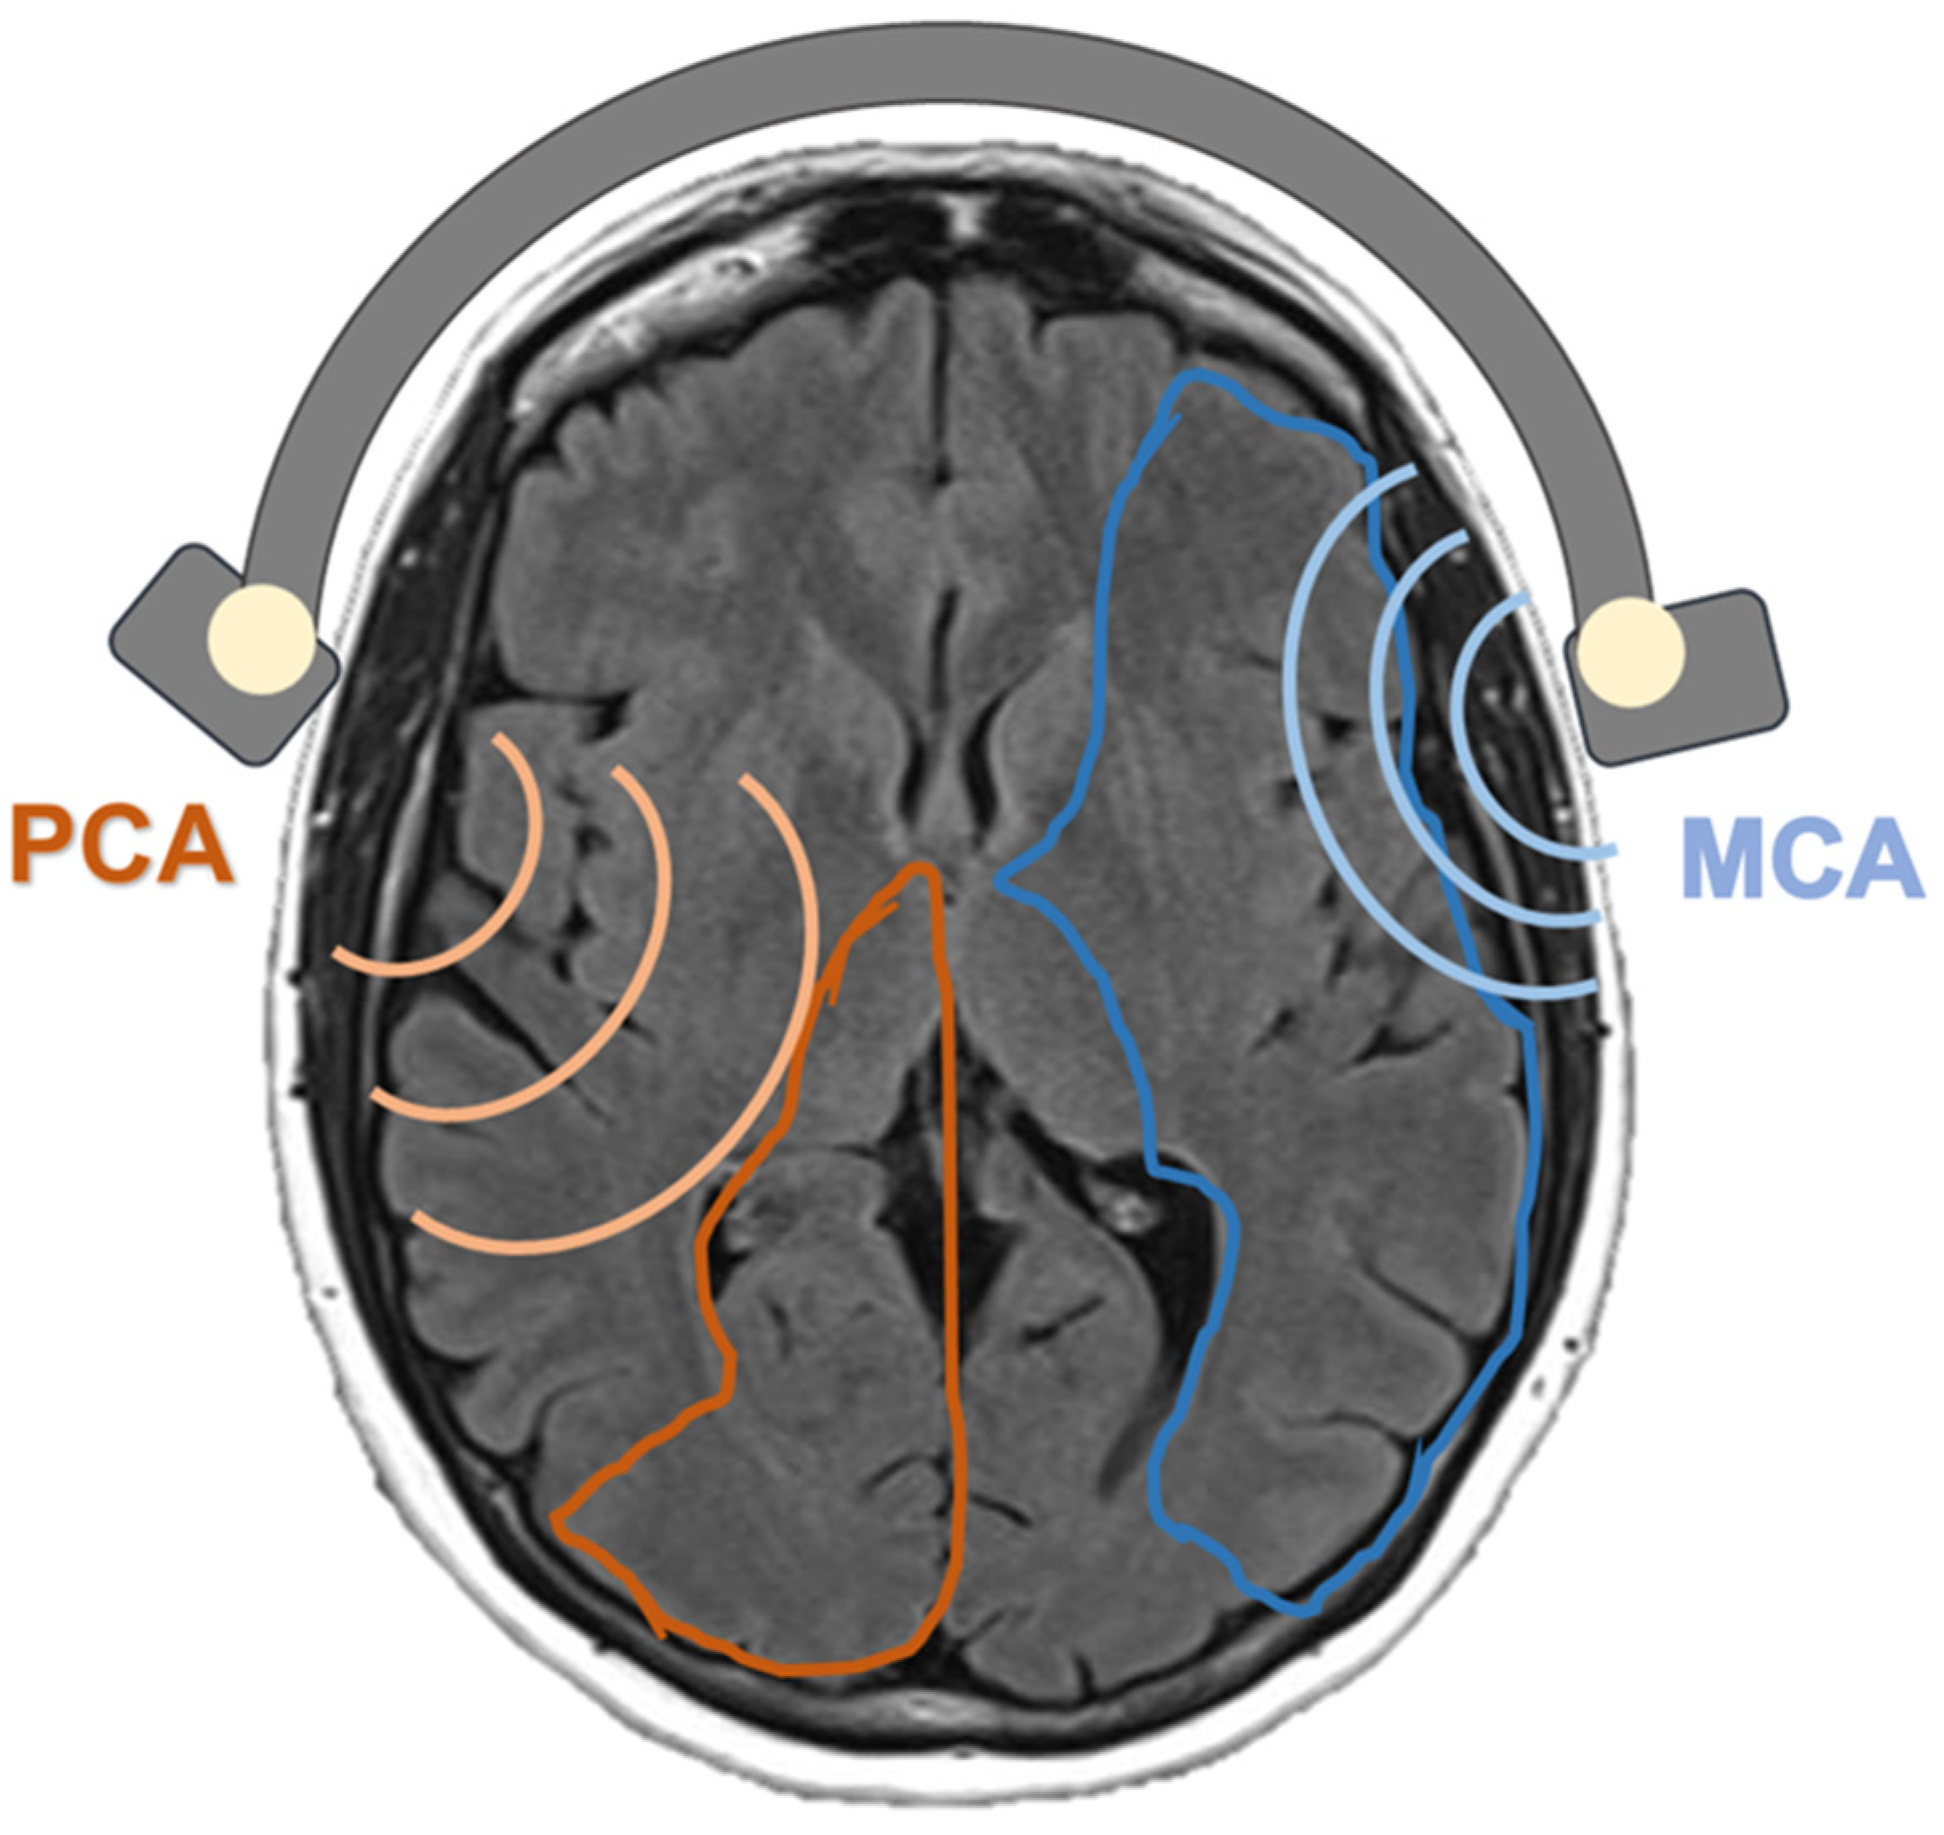

| MCA basal MFV cm/s, mean (SD) | 71.3 (14.1) | 65.9 (11.9) | 63.0 (10.0) | 0.201 |

| PCA basal MFV cm/s, mean (SD) | 45.7 (15.5) | 44.4 (12.4) | 44.8 (11.9) | 0.962 |

| BHI MCA %/s, mean (SD) | 1.56 (0.49) | 1.86 (0.52) | 1.59 (0.60) | 0.154 |

| BHI PCA %/s, mean (SD) | 1.49 (0.38) | 1.96 (0.66) | 1.49 (0.51) | 0.010 * |

| MCA territory, median (IQr) [range] | 1.6 (4.00) [0–12] | 1.0 (3.0) [0–16] | 2.5 (6.0) [0–16] | 0.237 |

| PCA territory, median (IQr) [range] | 0 (0) [0–5] | 0 (1.0) [0–2] | 0 (1.0) [0–3] | 0.159 |

| MCA territory, median (IQr) [range] | 0.016 (0.18) [0–1.4] | 0.016 (0.12) [0–7] | 0.09 (0.73) [0–3.7] | 0.130 |

| PCA territory, median (IQr) [range] | 0 (0) [0–0.57] | 0 (0.02) [0–0.6] | 0 (0.08) [0–0.31] | 0.093 |